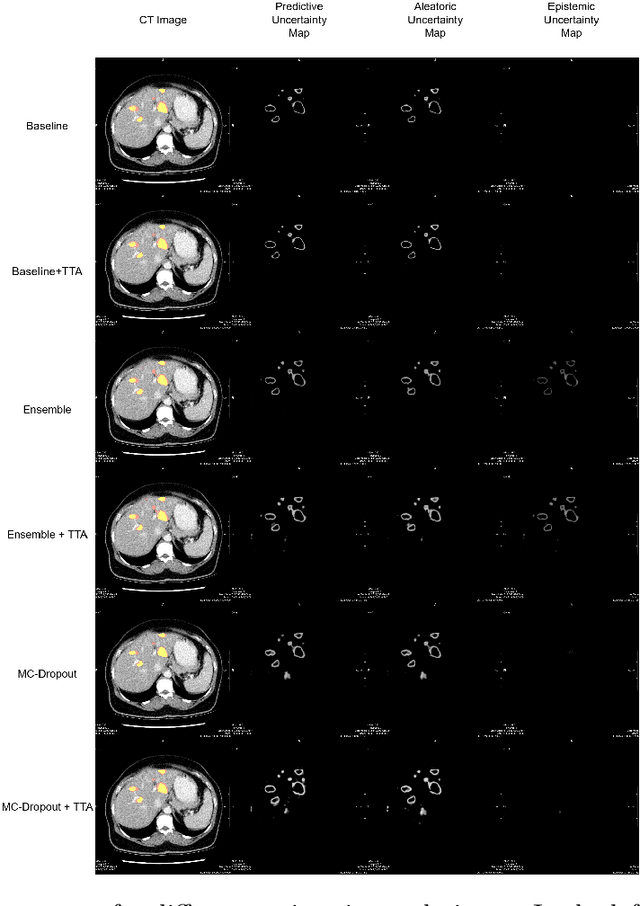

Abstract:Deep learning techniques show success in detecting objects in medical images, but still suffer from false-positive predictions that may hinder accurate diagnosis. The estimated uncertainty of the neural network output has been used to flag incorrect predictions. We study the role played by features computed from neural network uncertainty estimates and shape-based features computed from binary predictions in reducing false positives in liver lesion detection by developing a classification-based post-processing step for different uncertainty estimation methods. We demonstrate an improvement in the lesion detection performance of the neural network (with respect to F1-score) for all uncertainty estimation methods on two datasets, comprising abdominal MR and CT images respectively. We show that features computed from neural network uncertainty estimates tend not to contribute much toward reducing false positives. Our results show that factors like class imbalance (true over false positive ratio) and shape-based features extracted from uncertainty maps play an important role in distinguishing false positive from true positive predictions